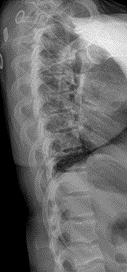

Radiographic examination of the thoracic spine was normal with no osseous abnormalities noted (Figure 1 and 2). The lumbar spine radiographic study revealed several unexpected findings.